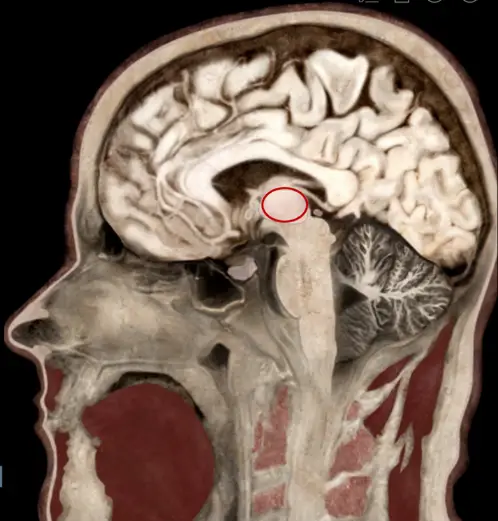

吳先生因車禍造成腦創傷並且昏迷,其兩側肢體出現僵直的姿勢(rigidity posture)反應,送醫經影像檢查發現其腦部有出血現象,受損位置如圖所圈示。下列何者為吳先生會出現的肌張力反應?

- 影像種類:這是一張腦部 MRI 的矢狀切面圖(Sagittal view)。

- 解剖定位:

- 影像中紅色圓圈圈選的構造位於**胼胝體(Corpus Callosum)的下方,以及中腦(Midbrain)**的上方。

- 該橢圓形灰質結構為視丘(Thalamus),屬於間腦(Diencephalon)的一部分。

- 在紅圈的下方,可以觀察到中腦的構造(包含四疊體/Colliculi),而紅圈顯然位於中腦之上。